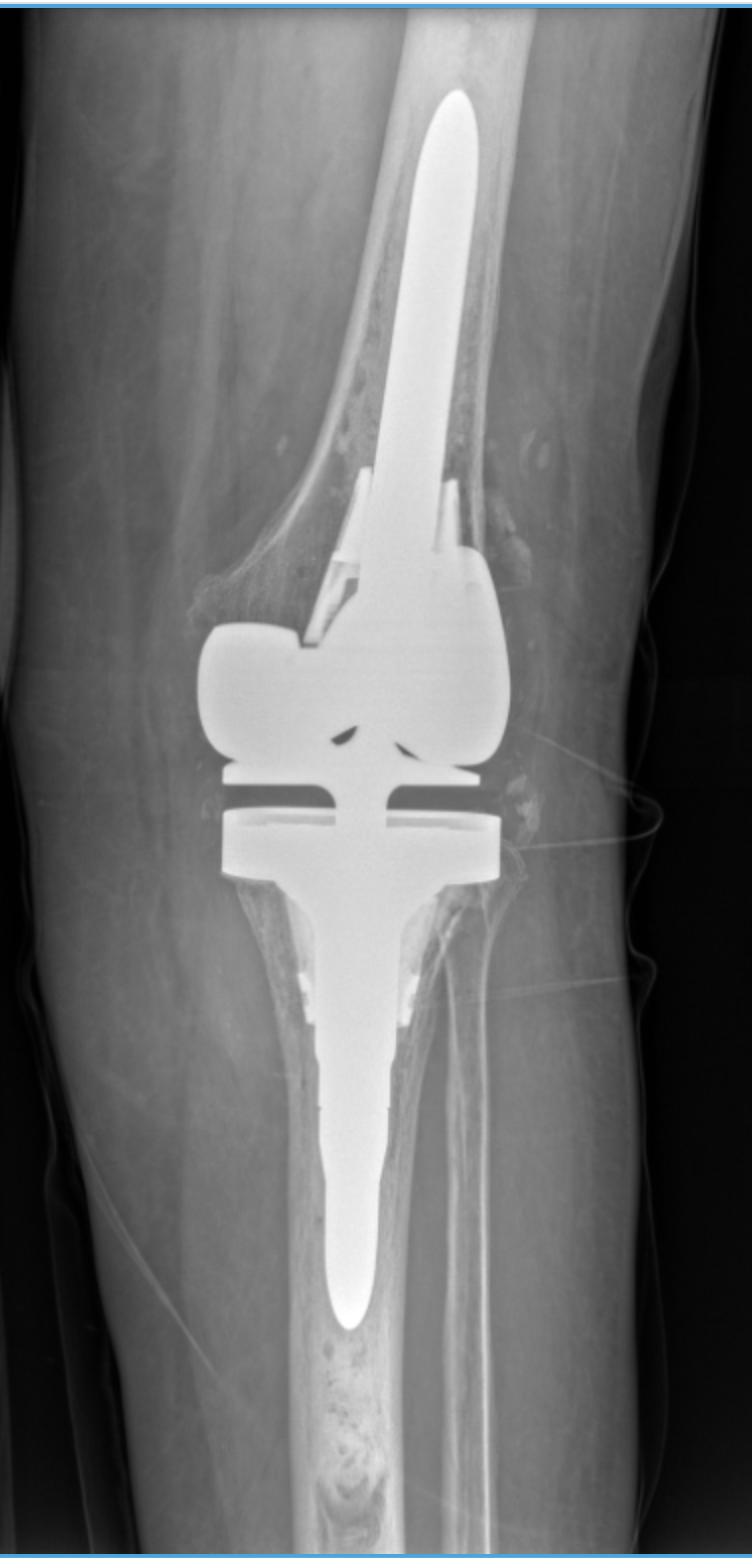

Dr. Movassaghi uses MAKO SmartRobotics™ to deliver customized knee replacements with exceptional accuracy. This advanced system allows him to plan every detail before surgery and make precise adjustments during the procedure—helping patients experience less pain, better mobility, and a quicker recovery.